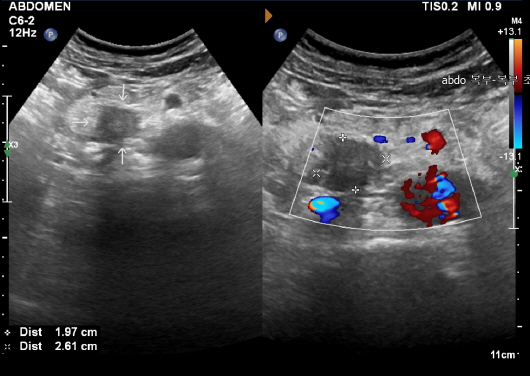

신장은 인체의 대사 노폐물을 제거하고 수분 및 전해질 균형을 유지하는 중요한 역할을 합니다. 신장에 문제가 발생하면 체내의 여러 기능이 부정적인 영향을 받을 수 있습니다. 복부 CT는 신장 결석, 신장 종양 및 기타 신장 관련 질환을 진단하는 데 도움을 줍니다.

신장 결석: 예방법과 치료 방법

신장 결석은 신장에서 형성된 경결된 물질로, 통증을 유발할 수 있습니다. 복부 CT는 결석의 위치와 크기를 정확하게 파악할 수 있으며, 이 정보를 바탕으로 적절한 치료 방법을 결정하는 데 매우 중요합니다. 결석이 발견되면, 물리치료, 약물 치료, 혹은 필요 시 수술이 고려될 수 있습니다. 신장 결석은 수분 보충과 균형 잡힌 식사를 통해 예방할 수 있으므로, 생활 방식의 변화 또한 동반되어야 합니다.